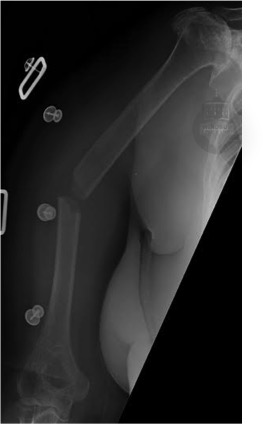

Midshaft Humerus fractures

Fractures of the humeral shaft are fairly common.  Elderly patients with weaker bone can break their arm with relatively low levels of force (e.g. a simple fall) , but younger patients tend to require powerful twisting or bending forces to break their humerus.

Most humeral shaft fractures do not require surgery.  If you don't require surgery you will be fitted with a humeral brace (a moulded plastic brace) and a sling.  This helps to stabilise your broken bone and allows you to move your elbow gently to avoid that getting stiff while your fracture heals.  Approximately 90% of well-selected humeral shaft fractures will heal without surgery.  It takes approximately 12 weeks for bony healing in most cases.

- Transverse fractures carry a higher risk of non union if left alone, so in Mr Granville-Chapman's hands, these are normally fixed.

- Displaced fractures that lie near the elbow will normally heal, but deformity may be hard to tolerate and elbow stiffness is a problem.  Again, Mr Granville-Chapman will normally offer surgery      to fix these injuries.

- Some fractures are hard to control with a brace because of their location near the armpit.  If an acceptable position cannot be maintained in a brace, you may require surgical fixation.